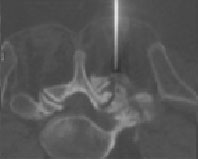

Injektion Facettengelenk Lendenwirbelsäule (Spritze in das kleine Wirbelgelenk unter CT-Kontrolle)

Nadelspitze exakt im Gelenkspalt des kleinen Wirbelgelenkes zwischen 5. Lendenwirbelkörper und Kreuzbein

Nach Injektion von Kortison, Lokalanästhetikum und Kontrastmittel in das kleine Wirbelgelenk, Verteilung des Medikaments im Gelenkspalt (wegen altersbedingten Löchern in der Gelenkkapsel) auch epidural